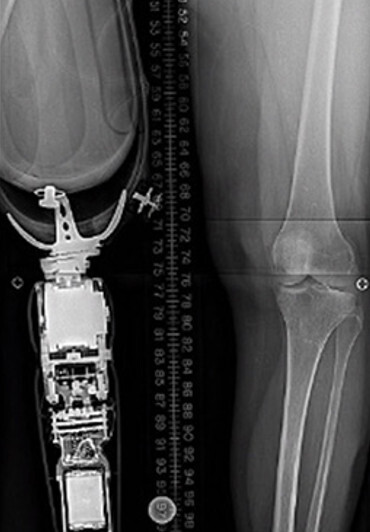

Our work begins with a consultation with the surgeon and CT scan modeling of the patient’s anatomy.

This is the basis for a design tailored to the patient and digital manufacturing.

Advanced osseointegration is designed into every implant. Our manufacturing process allows geometry and surface texture to be tuned to encourage bone growth for maximum fixation. We are osseointegration specialists.